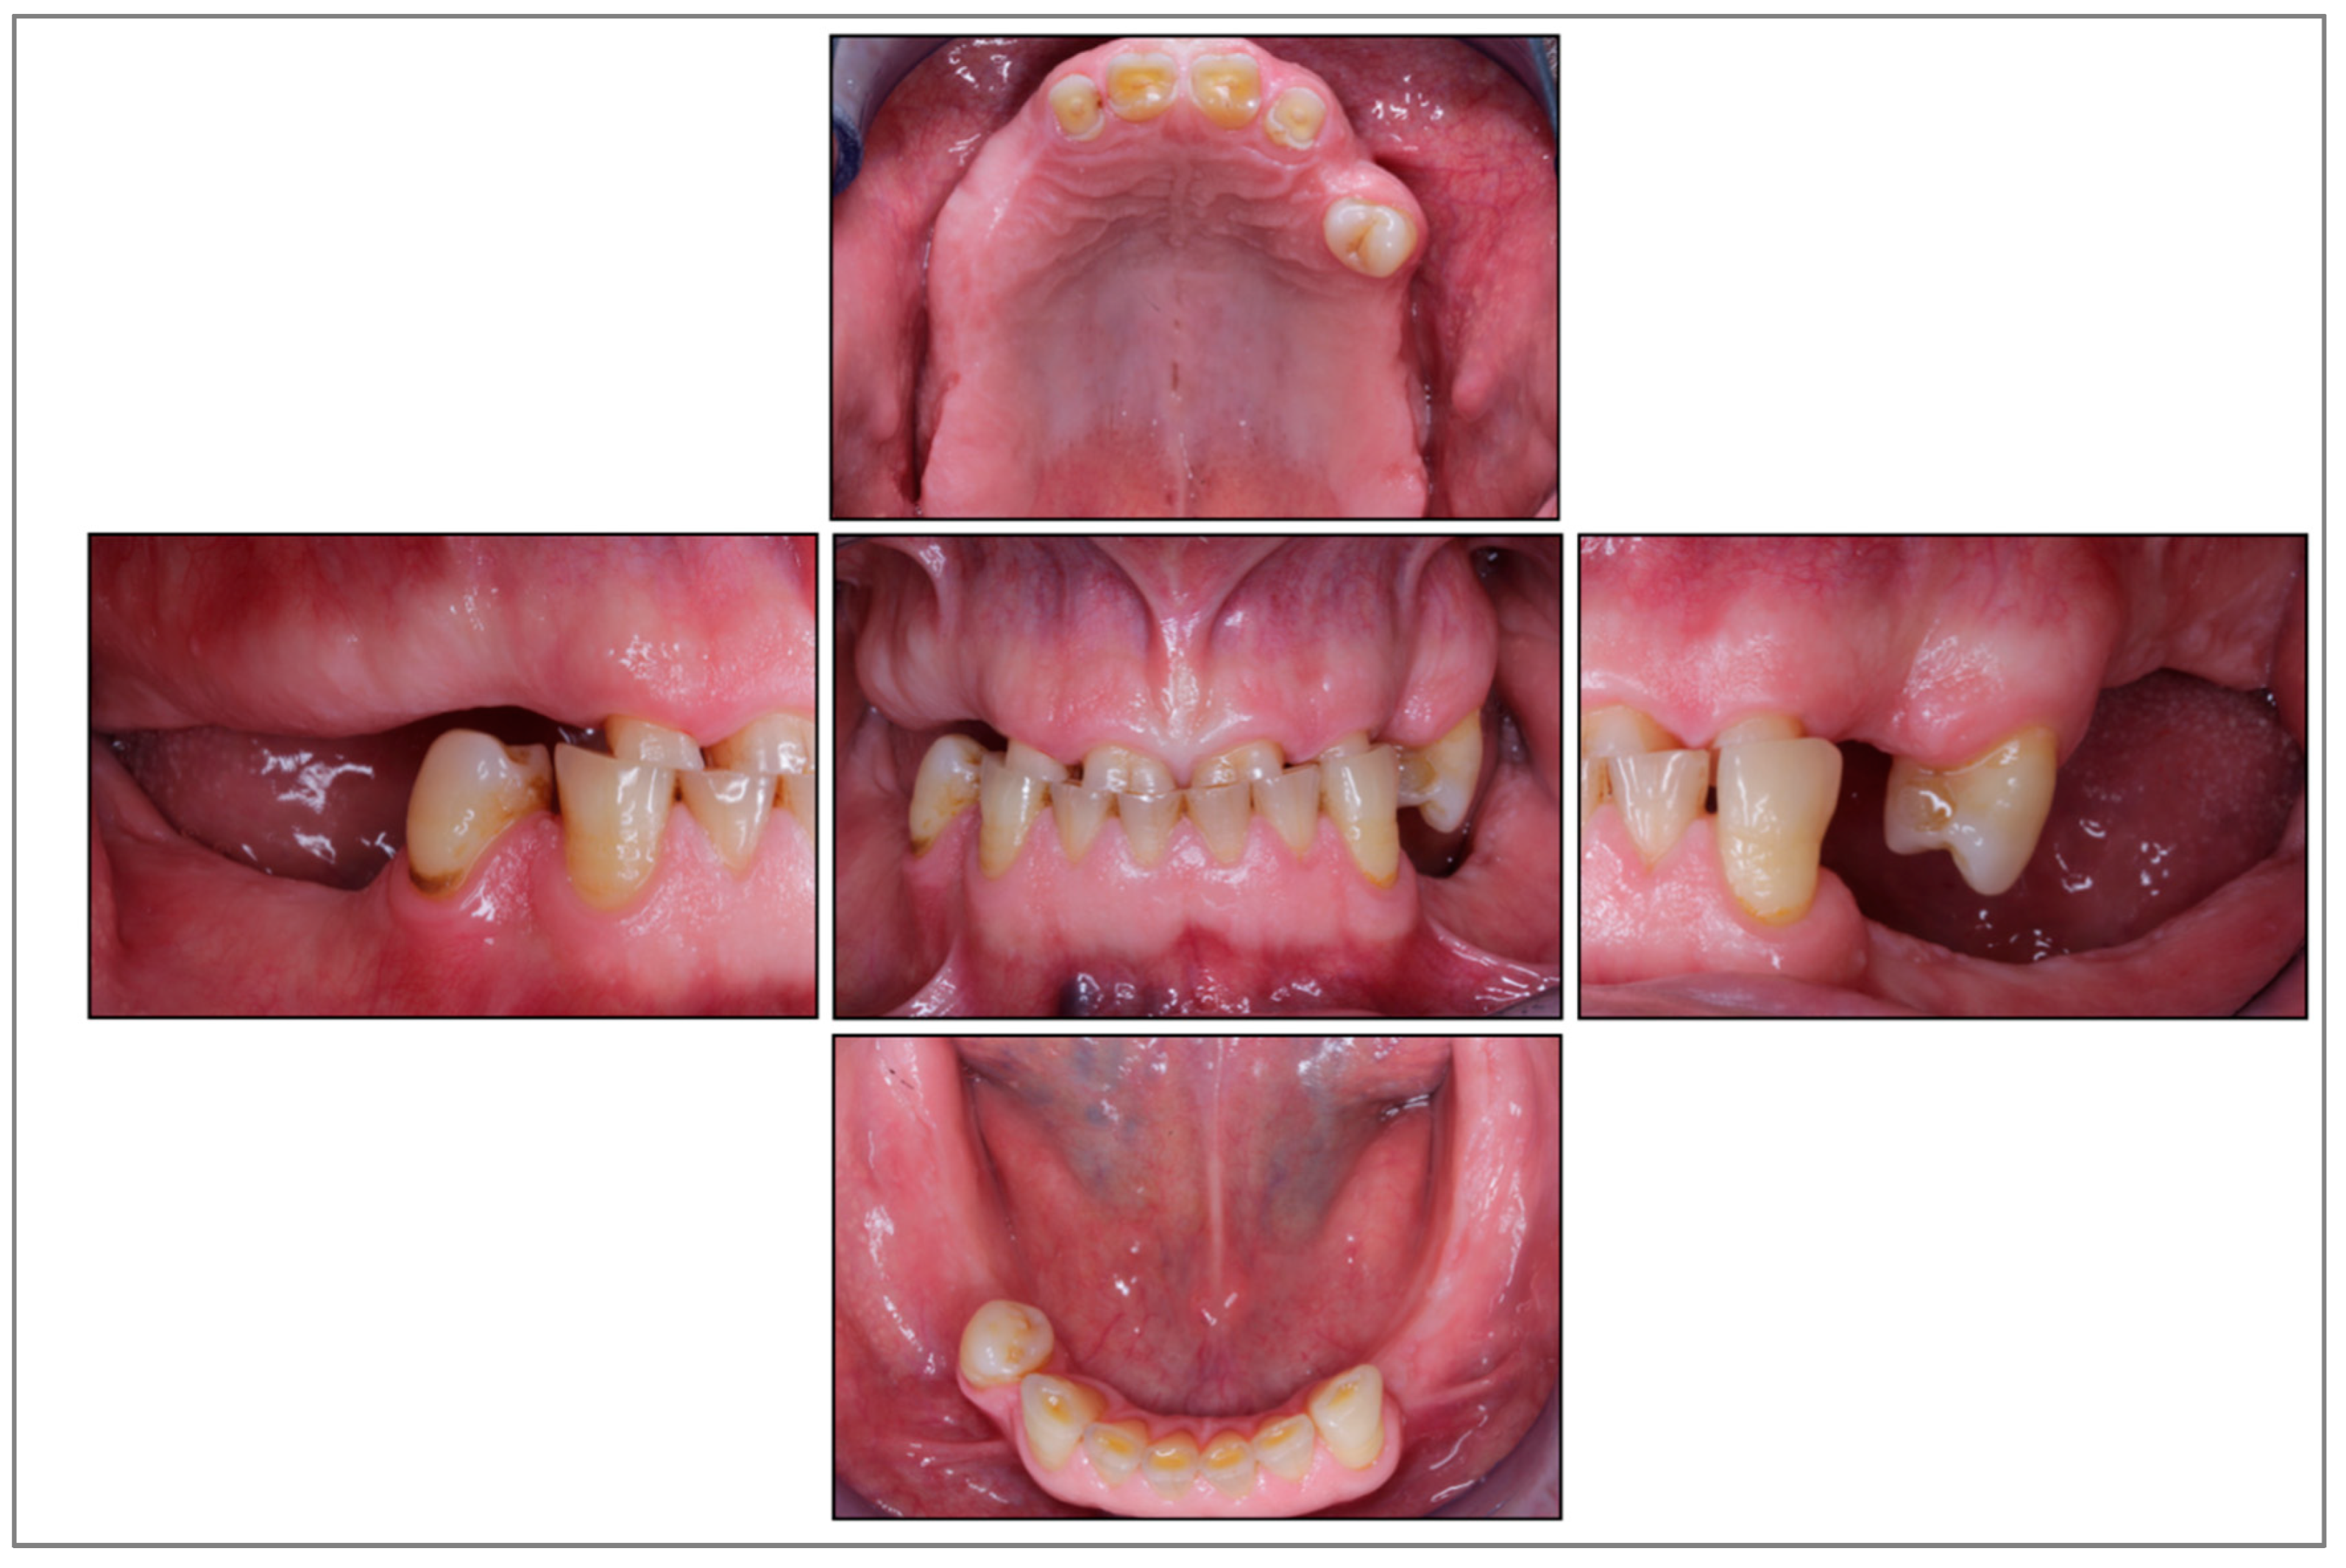

A 52-year-old male patient introduced himself to the University Center for Dental Medicine Basel (UZB) with the request for a prosthetic rehabilitation. He was in general good health, had never smoked, and related previous tooth loss to caries lesions. Initial periodontal and radiographic screening revealed healthy conditions of the remaining dentition with severe tooth wear and a collapsed bite (Figure 1).

Figure 1. Clinical situation before treatment.